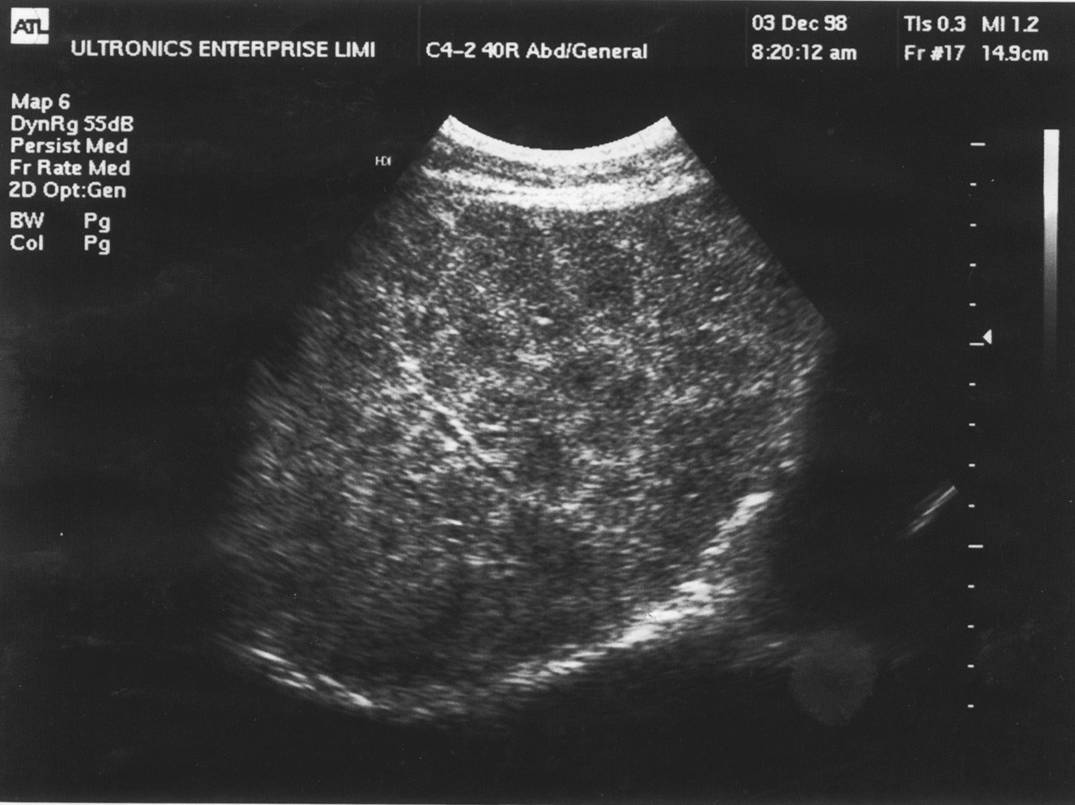

声像表现

急性期无特异性声像,肝脏稍大,光点较密

慢性期及晚期

1、肝脏缩小或不规则。肝表面不光整,呈锯齿状。

2、肝脏实质内回声:呈现网格状回声增强区,增强光带将肝实质分隔成<3cm的小区,小区形态不规则,内部回声不均匀。

3、肝硬化表现

4、脾大较显著